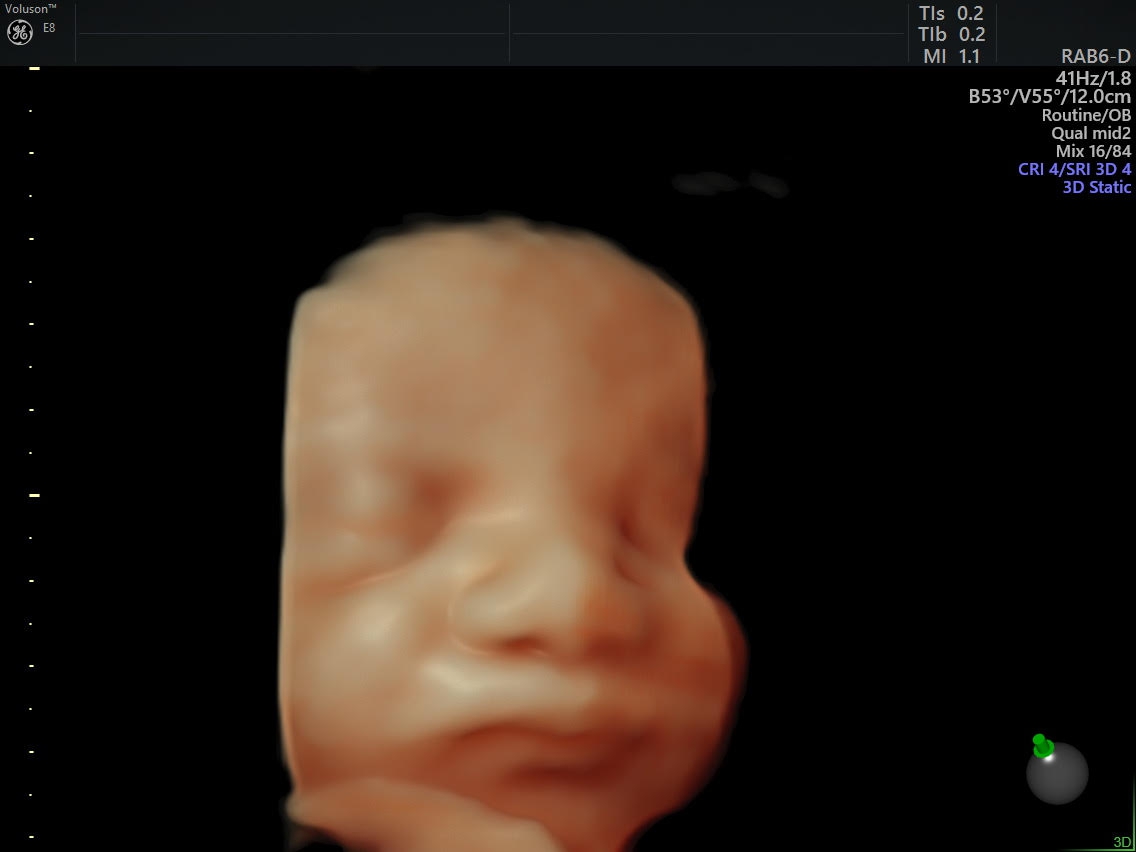

Cason Joseph   27/05/2022 00:00

Dört boyutlu ultrason ile iyi kalitede bebek fotoğrafları elde edilebilmesi; Erkek bebek olması i̇çin dua. Ağırlıklı olarak kız çocuklarında görülse de erkek çocuklarında da görülebilmektedir. Bebek kız ise, ultrason görüntüsünde alt. Gebelik döneminde erkek çocuğun ya da kız çocuğun erken dönemde. Gebelikte erkek bebek ultrason görüntüleme işlemlerinde erkek bebeğin penis ve testis görüntüleri oluşması yeterlidir. Videodaki bebek 19 haftalıktır ve anne karnında erkek bebeğin ultrasonda nasıl görüneceğine dair fikir oluşturması için paylaşılmıştır.19 haftalık gebelik il. Cihaz jelin sürüldüğü bölgede gezdirilerek cihazdan gelen analizler. Erkek bebeğe sahip olacak anne babalar için 2022 en çağdaş ve farklı erkek bebek isimleri sizler için derledik.

Ultrasonda erkek bebek belirtileri nelerdir? Bebeklerinin yüzünü görmek anneyi ve babayı mutlu etmektedir. Özel hastanelerdeki ayrıntılı renkli ultrason güncel ücretleri şöyledir: